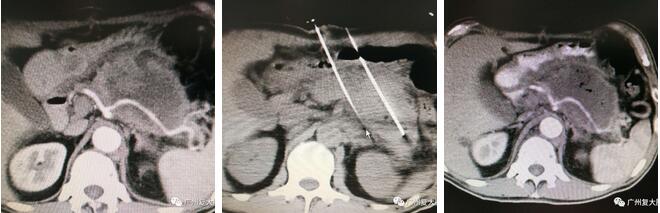

左中右圖分別是術前、術中、術後CT圖

經過麻醉後,患者逐漸進入手術狀態。在B超加CT的引導下,腫瘤清晰地呈現在屏幕上,牛立志博士熟練地在患者的腫瘤處插上兩根電極針。"如何最大限度地消融腫瘤,包括腫瘤的邊緣部位,而不傷及週圍的血管,這是考驗外科醫生的經驗水平。"

該手術的難點還在於,腫瘤包遶了兩根腹腔幹動靜脈,還與脾胃、結腸、空腸、肝髒相粘連。"布針時要儘量靠近邊緣,不能觸及到週圍的髒器,同時要不斷調整電極針的進針方向與角度,避免插到血管。"牛立志告訴筆者,除了經驗以外,手術對外科醫生的細心和判斷也有更高的要求。

平日的納米刀手術大約在一小時左右可完成,而這場手術卻持續了三個小時。下午2點,手術團隊為李興順利消融了巨大的胰腺癌腫瘤。"手術已經順利完成。"當牛立志博士告知門外家屬那一刻時,他們懸着的心終於放了下來。